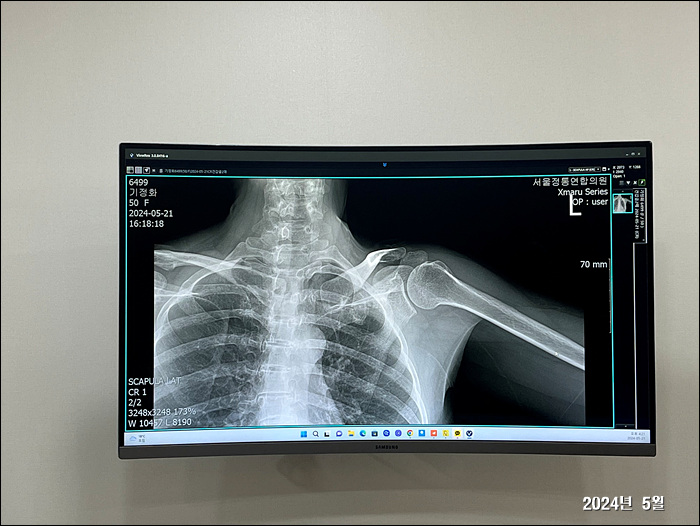

2024. 5. 23.

왼쪽팔이.... 갈수로 굳어지고 아프다...=..=

이렇게 운동하면 좋다길래 밤마다 온가족이 나와서 운동기구로 팔을 풀어준다.

덩달아 제민이도 나와서 노는데~ 좋단다 ㅋㅋㅋ